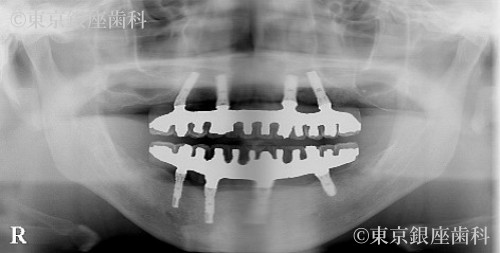

施術内容 ワンデイインプラント

ワンデイインプラントの特徴である少ないインプラントの本数による全顎的な口腔機能の回復と、人工歯によって受け口の改善もできた口腔機能と審美が回復した症例です。